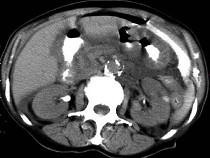

问题 男,44岁,突然中上腹痛,压痛,反跳痛,腹肌紧张,发热,白细胞计数升高,CT检查如图,最可能诊断是 ( )

选项 A.急性胰腺炎 B.慢性胰腺炎 C.胃小弯溃疡穿孔 D.胰腺癌 E.胃癌

答案 C